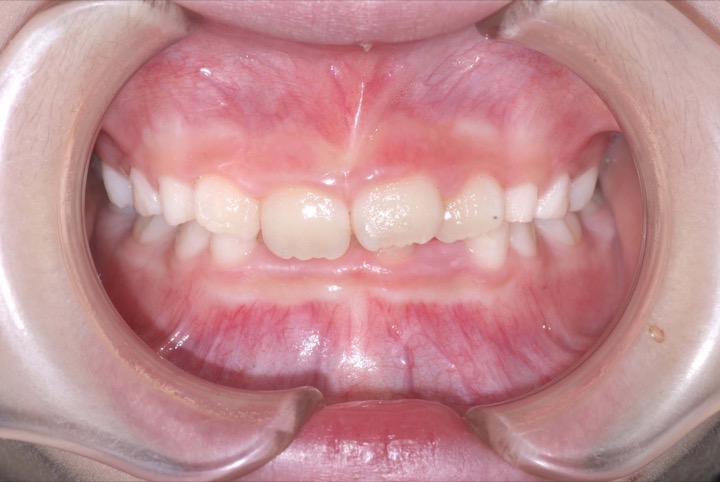

初診時年齢9才の女子で上下顎前歯の部の乱ぐいを気にして来院されました。

検査の結果、叢生と過蓋咬合を伴うアングルⅠ級不正咬合と診断しました。